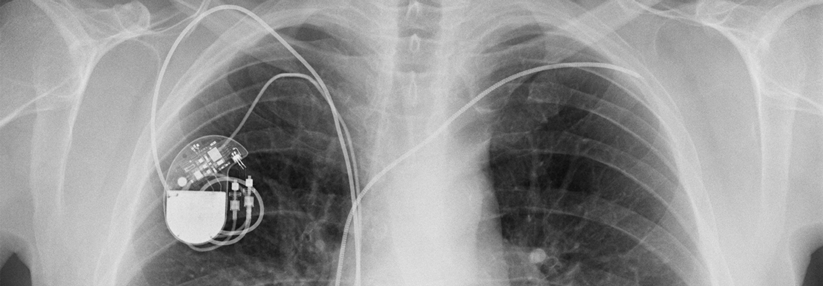

Für wen kommt ein Herzschrittmacher infrage? Für wen kommt ein Herzschrittmacher infrage? © iStock.com/Jan-Otto

Implantationen von Herzschrittmachern und Kardioverter-Defibrillatoren zählen zu den häufigsten Operationen in Deutschland. Mehr als 100 000 wurden im Jahr 2016 durchgeführt. Die Indikationen sind relativ eng gefasst, denn nicht jeder profitiert von den Geräten.